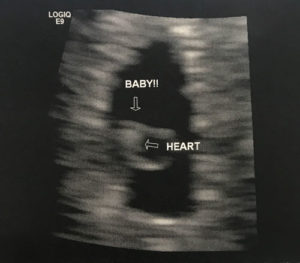

Successful Essure Reversal Pregnancy Confirmed: Saw Heartbeat!

Essure Reversal Pregnancy Confirmed By Ultrasound

We saw the heartbeat yesterday. The baby is measuring 5weeks and 6days.

Patient age: 28

Tubal ligation type: Essure

Patient hometown: Davenport, Iowa